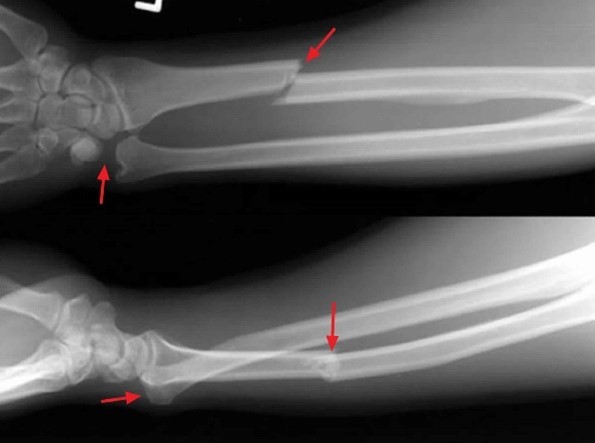

What fracture is this?

Galeazzi Fracture

Radial fracture and radial-ulnar dislocation